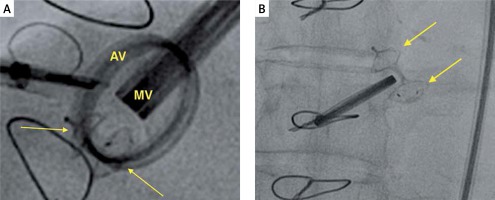

To ensure optimal spatial and temporal resolution, we acquire the smallest possible volumes containing the complete PVL channel in an ECG-gated, single-beat zoom 3D High Volume Rate (HVR) mode with color doppler (CD). Such visualization of PVL opacification by CD-mapped flow turbulence is used for detailed PVL anatomy analysis. With acquired volume being replayed in the multiplanar presentation the PVL channel is reoriented within the three perpendicular planes until two of them are positioned parallel to the flow direction while the third one is perpendicular and at the level of the vena contracta (VC) – Figure 1. Pivotal for the device choice are the cross-sectional area (CSA) and the minimum (width – W) and maximum (length – L) diameters of VC, all measured on the image frozen at the time of maximum paravalvular backflow. Analogously, the channel depth, understood as the distance between cavities of the left ventricle (LV) and left atrium (LA), can be verified (Figures 2 A and B). The size and number of plugs are chosen in previously described manners according to either CSA for AVP III [9, 11] or W and L for PLD [12].

A – Fluoroscopy image of a properly expanded PLD (PLD closing mitral PVL, arrows pointing at the discs of PLD). B – Fluoroscopy image of a deformed PLD (arrows pointing at the discs of PLD)

MV – mitral prosthetic valve, AV – aortic prosthetic valve.